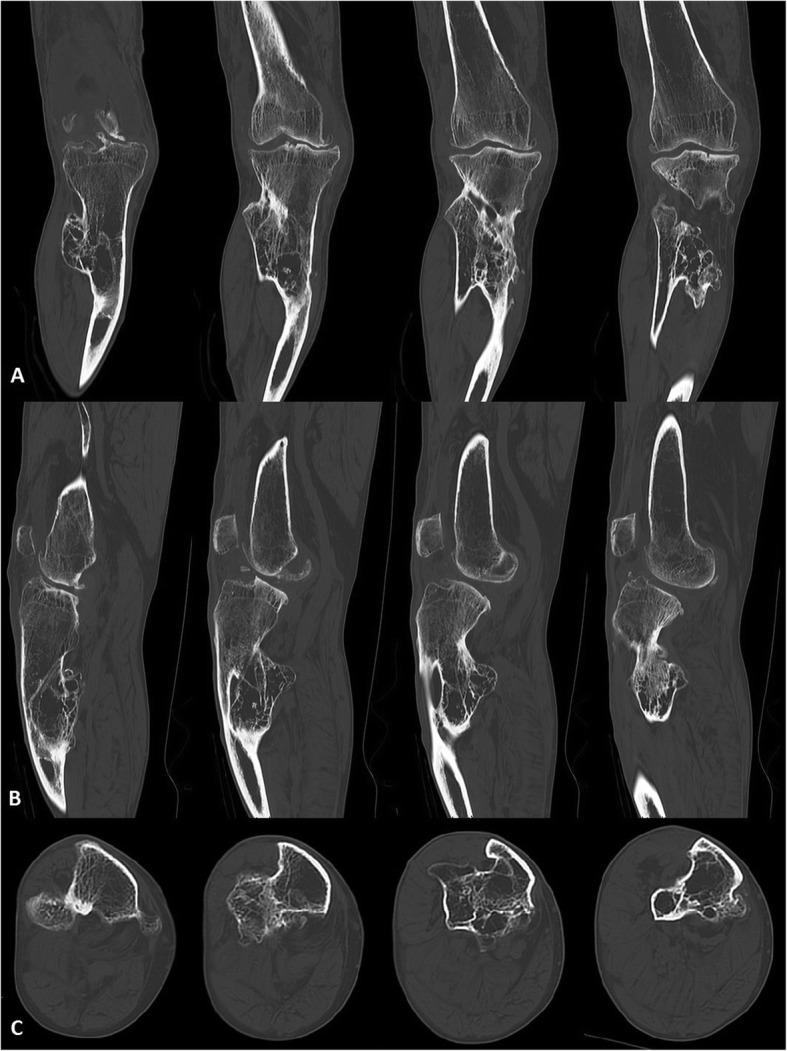

多灶性遗传性骨软骨瘤病伴多轴向肢体畸形患者行全膝关节置换术联合胫骨干骺端截骨术:1 例报告

Total knee arthroplasty with simultaneous tibial shaft osteotomy in patient with multiple hereditary osteochondromas and multiaxial limb deformity - a case report.

Hereditary multiple osteochondromas (hereditary multiple exostoses, HME) is a rare genetic disease characterized by the development of benign osteocartilaginous tumors that may cause severe limb deformities and early onset osteoarthritis. Total knee arthroplasty (TKA) is the method of choice for the treatment of advanced gonarthrosis, however the surgical management with coexisting severe axial limb deformity remains unclear.

CASE PRESENTATION

65-year-old man with HME and extra-articular multi-axial limb deformity was admitted to the orthopedic department due to chronic knee pain and limited range of motion caused by secondary osteoarthritis. Regarding to the clinical and radiological examinations, after preoperative planning he was qualified to a one-stage TKA combined with tibial shaft osteotomy (TSO). In a one year follow-up full bone union was confirmed with no signs of implant loosening or prosthesis displacement. Patient was very satisfied, did not report any joint pain and has sufficient range of motion without knee instability.

CONCLUSION

The improvement of mechanical axis during TKA is a crucial factor for achieve operative success and long implant survival. Despite the higher risk of complication rate in comparison to two-stage treatment, one-stage TKA with simultaneous TSO should be a considerable method for patients with osteoarthritis and multiaxial limb deformities. This method can give a good clinical and functional outcomes, however should be performed subsequently to careful preoperative planning and proper patient qualification.